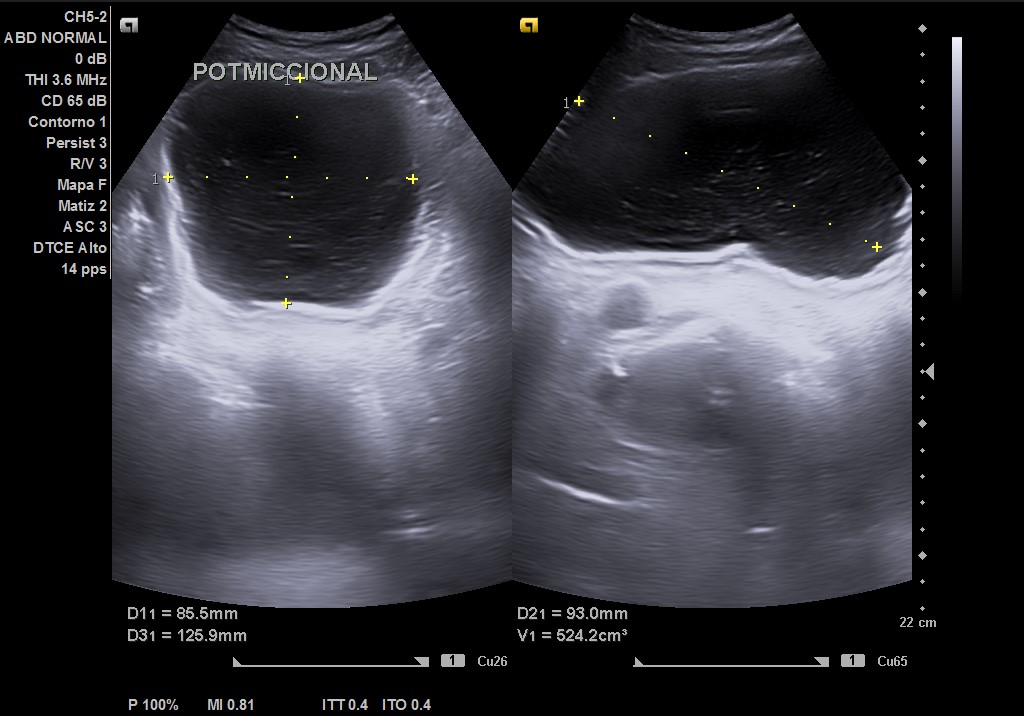

Ecografía tras ingerir 1 litro de agua y sin orinar posteriormente, con sonda convex: se visualiza vejiga repleccionada hasta 2 cm del ombligo, con > 550 cc (difícil de cuantificar por gran tamaño). Residuo postmiccional 525 cc, paredes de vejiga con signos de lucha, divertículo e imagen de «centelleo» en desembocadura de uréter derecho, pero sin afección del jet ureteral ipsilateral. Próstata de 67 cc aproximadamente, que protruye en vejiga. Riñones con ecoestructural normal sin dilatación en vía excretora.